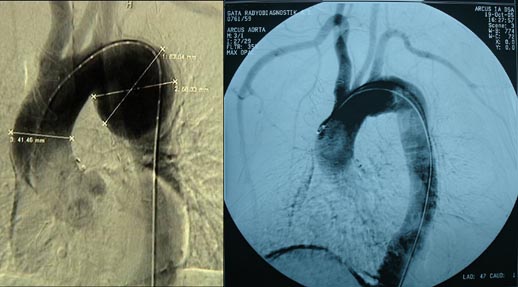

Kliniğimizde ameliyat edilen desenden aort anevrizmalı bir hastanın ameliyat öncesi ve sonrası aorta görüntüleri. Bu ameliyatta kalp akciğer makinesi kullanılarak hastanın vücut sıcaklığı 19?C’ye kadar soğutulmuş ve 30 dk süreyle dolaşım tamamen durdurulmuştur.